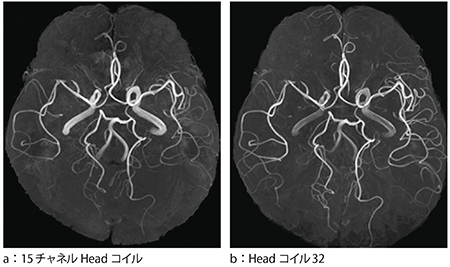

図7はMRAの画像比較であるが,特に頭部周辺の末梢血管部において感度の向上が顕著であり,描出能が大きく向上している。

図7 画像の比較(MRA)